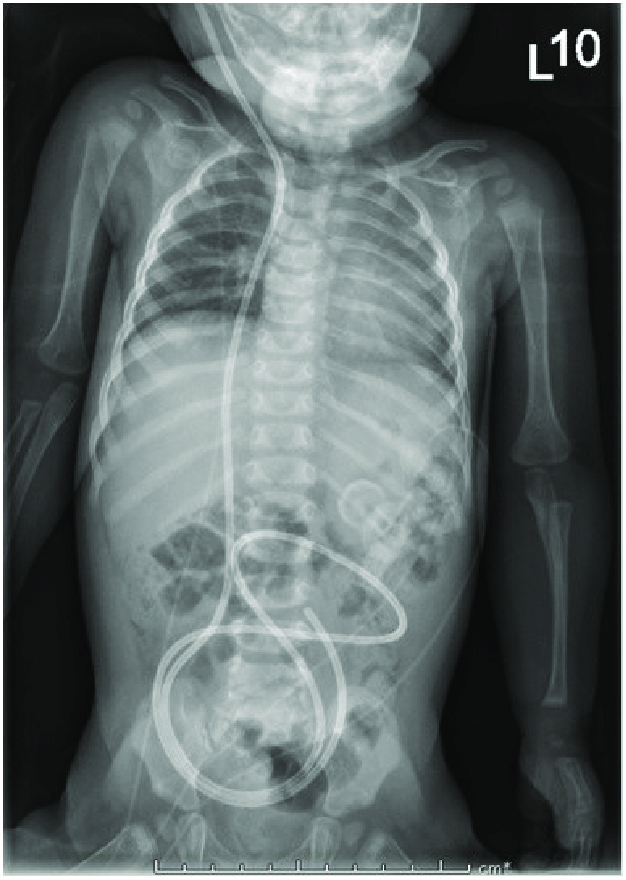

The attached image demonstrates ventriculoperitoneal shunt as visible on radiograph. Reference: https://www.researchgate.net/publication/329438533_Importance_of_Preoperative_Evaluation_in_the_Diagnosis_of_Ventriculoperitoneal_Shunt_Malfunction_in_an_Infant_with_Hydrocephalus/figures?lo=1&utm_source=google&utm_medium=organic